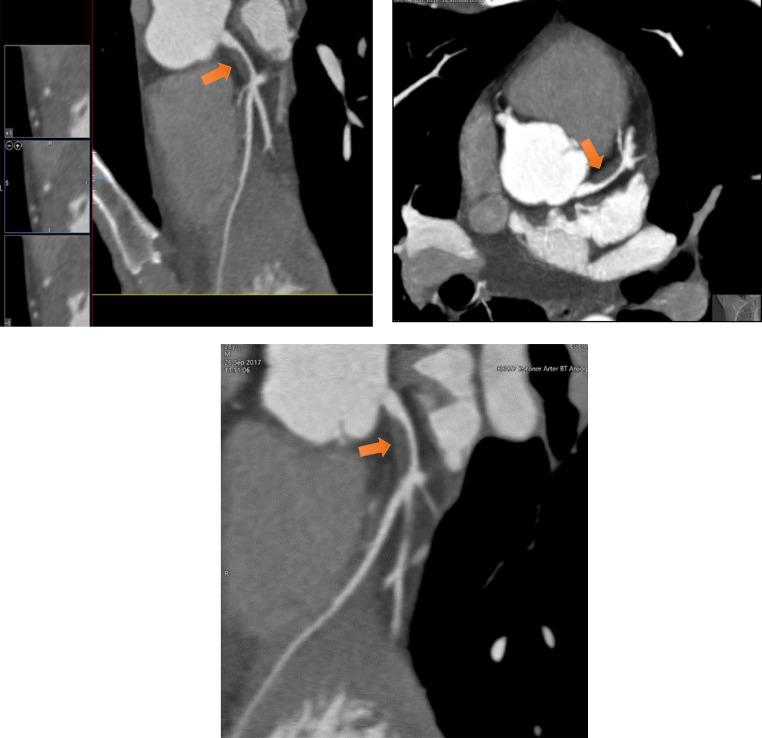

Blunt chest trauma may cause variable degrees of thoracic injuries. Most of the patients may remain asymptomatic after sustaining blunt chest trauma. But in rare instances, life-threatening conditions such as coronary artery dissection may occur. The authors present a 29-year-old male adult with persistent chest pain following blunt trauma with a rise in cardiac troponins and elevated ST segment in ECG. Coronary CT and conventional angiography demonstrated dissection of the left main coronary artery. It is deemed necessary to suspect cardiac injury in patients with a history of blunt chest trauma in appropriate clinical settings. Early recognition of coronary artery dissection is vital to reduce morbidity and mortality. ECG combined with cardiac enzymes can be essential tools helping the physicians raise the suspicion towards a cardiac injury followed by cross-sectional and conventional angiographies for confirmation.

钝性胸部创伤可能导致不同程度的胸部损伤。大多数患者在遭受钝性胸部创伤后可能没有症状。但在极少数情况下,可能会出现危及生命的情况,如冠状动脉夹层。作者报告了一名29岁成年男性,在钝性创伤后持续胸痛,心肌肌钙蛋白升高,心电图ST段抬高。冠状动脉CT和传统血管造影显示左主干冠状动脉夹层。在适当的临床环境中,有钝性胸部创伤史的患者有必要怀疑心脏损伤。早期识别冠状动脉夹层对于降低发病率和死亡率至关重要。心电图结合心肌酶可能是帮助医生提高对心脏损伤怀疑的重要工具,随后通过横断面和传统血管造影进行确诊。